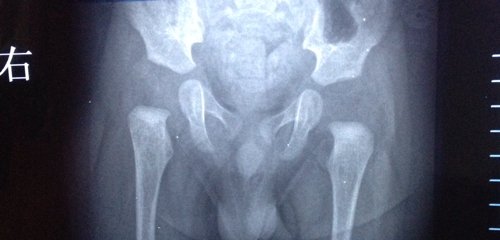

五个月男宝宝,仰着平躺会发现左腿比右腿长,并且右腿有时换尿布会有嘎嘣响声,右侧胳膊也会偶尔有响声。俯卧看孩子腿纹明显不对称,详见图。到医院拍片,医生说髋关节发育不良,让带吊带恢复,可是孩子不愿意带那个东西,还总是不断频繁蹬腿,心里担心,怕留下后遗症,烦请各位专家帮忙看看,孩子是否必须带吊带?情况严重吗?请推荐个好的治疗方法,谢谢!